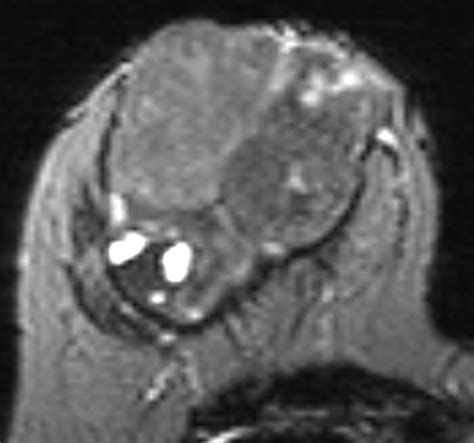

A Phyllodes tumor breast is a rare type of fibroepithelial tumor that originates in the connective tissue of the breast, known as the stroma. Unlike breast carcinomas, which arise from the milk ducts or lobules, these tumors grow within the supportive structural tissue. The term "phyllodes" comes from the Greek word for "leaf-like," which describes the specific pattern in which these tumors grow under a microscope.

These tumors are generally characterized by their rapid growth. While the vast majority are benign, some can be borderline or malignant. Because they can grow quite large and may recur if not completely removed, accurate diagnosis and appropriate surgical intervention are essential.

To differentiate a Phyllodes tumor breast from other breast conditions, clinicians employ a multi-modal diagnostic approach. Since imaging alone cannot definitively distinguish a phyllodes tumor from a fibroadenoma, a biopsy is typically required.

2. Imaging (Mammography/Ultrasound): Provides detailed views of the tumor's size, shape, and borders.

The definitive treatment for a Phyllodes tumor breast is surgical excision. Because these tumors have a tendency to recur, surgeons aim for "wide margins." This means removing the tumor along with a rim of healthy, surrounding breast tissue to ensure that no tumor cells are left behind.